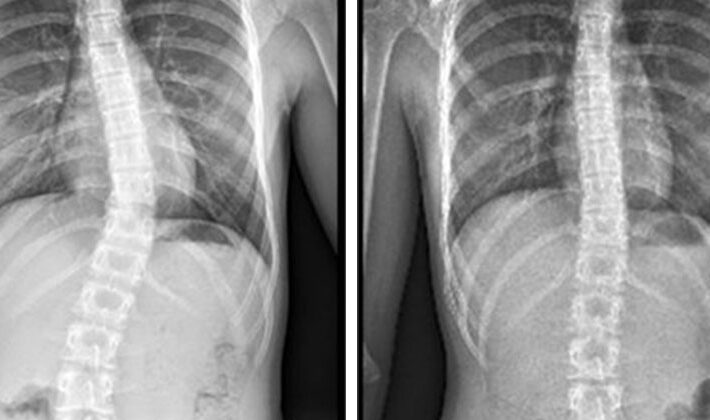

يُعد اعوجاج العمود الفقري، أو ما يُعرف طبيًا بـ”الجنف”، من الحالات الشائعة التي تصيب الأطفال والمراهقين، وقد تستمر أحيانًا حتى سن البلوغ. ورغم أن بعض الحالات الشديدة قد تحتاج إلى تدخل جراحي، فإن الغالبية يمكن علاجها أو السيطرة عليها بطرق غير جراحية فعالة وآمنة.

الجنف هو انحناء غير طبيعي في العمود الفقري نحو الجانبين، وقد يأخذ شكل “S” أو “C”. يظهر عادةً في سن المراهقة، وقد يكون السبب غير معروف (مجهول السبب)، أو ناتج عن أمراض عصبية أو عضلية أو تشوهات خلقية.

العلاج غير الجراحي للجنف يُعتبر خطوة فعالة وآمنة خاصة في المراحل المبكرة. يشمل خيارات متعددة مثل العلاج الطبيعي، التمارين العلاجية، الحزام الطبي، . المفتاح هو التشخيص المبكر واتباع خطة علاجية منتظمة بإشراف مختصين.

الاعوجاج حالة مستمرة قد تحتاج تدخلًا في مراحل مختلفة من العمر. وبفضل وجود تقنيات التصنيف المعتمدة ، يمكن للأطباء تصميم خطة علاجية مخصصة تضمن تدخلاً جراحيًا عند الضرورة أو العلاج غير الجراحي قبل ذلك، لتفادي الاضطراب في الوظائف التنفسية أو أي أعراض متأخرة. فريقنا المحترف يضم نخبة من الأطباء والمتخصصين الذين يجمعون بين الخبرة والاحترافية لتقديم خطة علاجية شاملة ومخصصة لحالتك، تضمن السيطرة على الانحناء ومنع زيادته.